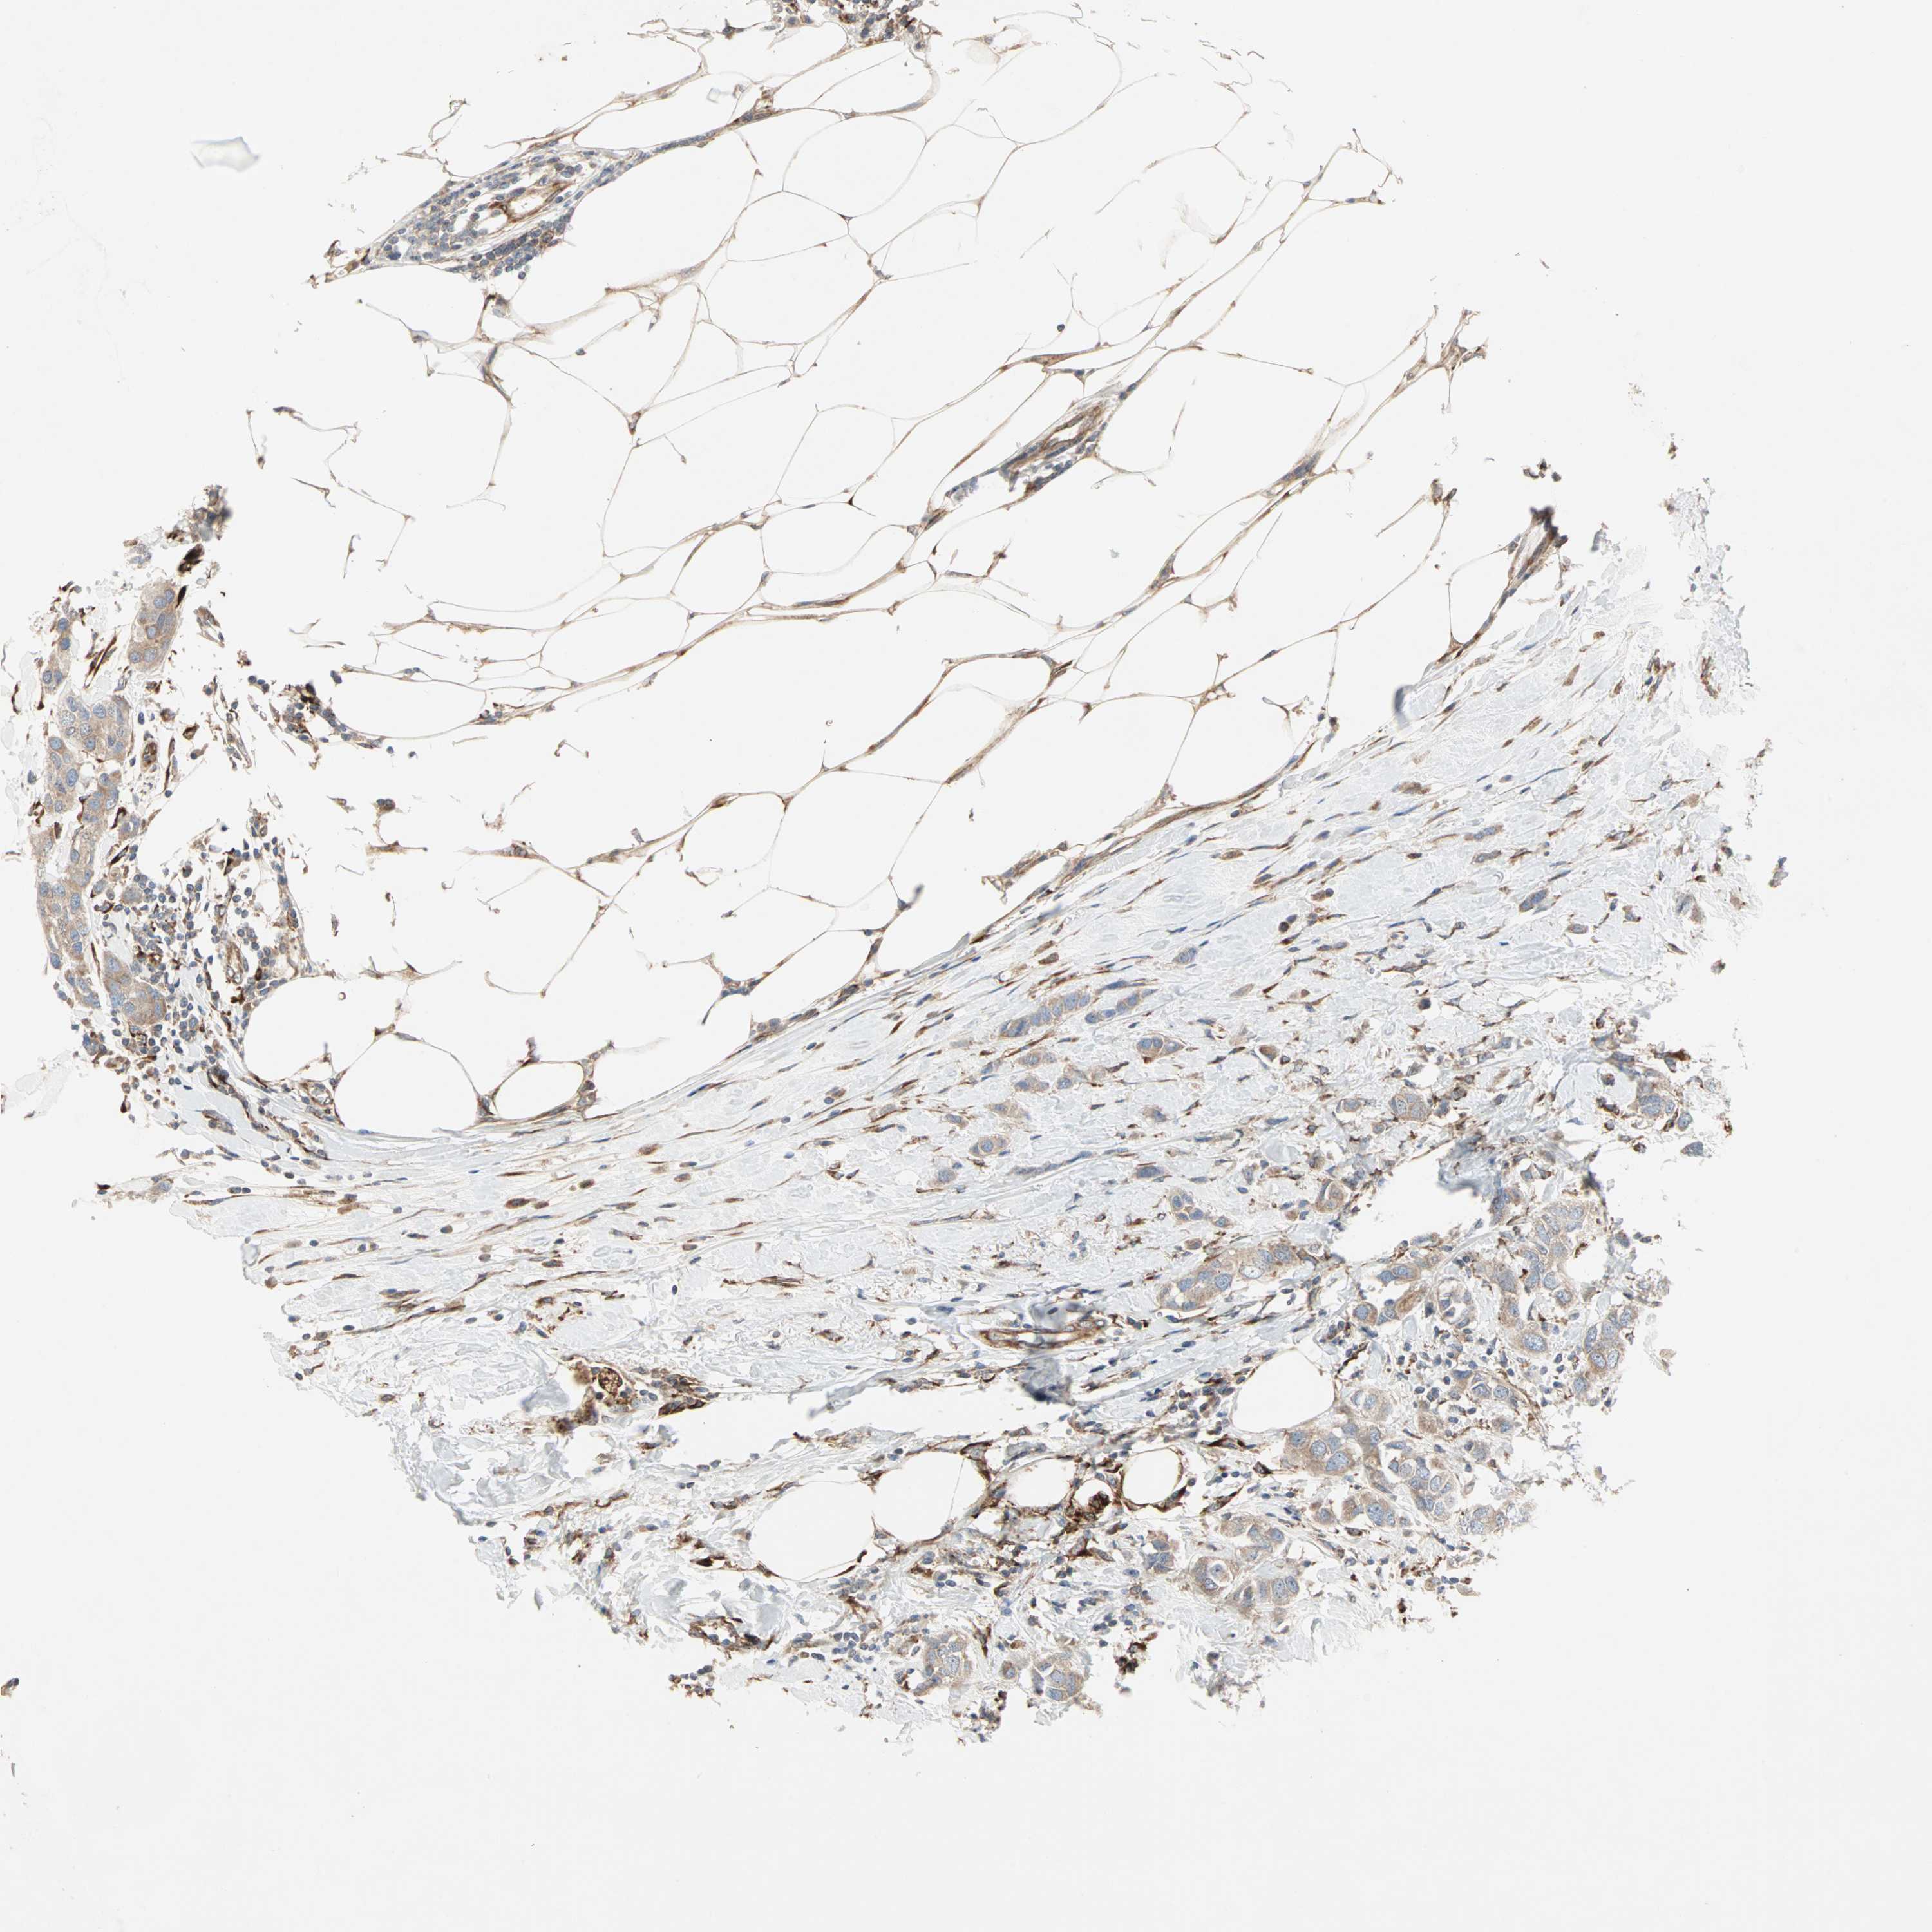

CANCER BREAST CANCER Show tissue menu

BRCA TCGA BRCA VALIDATION PROTEIN EXPRESSION